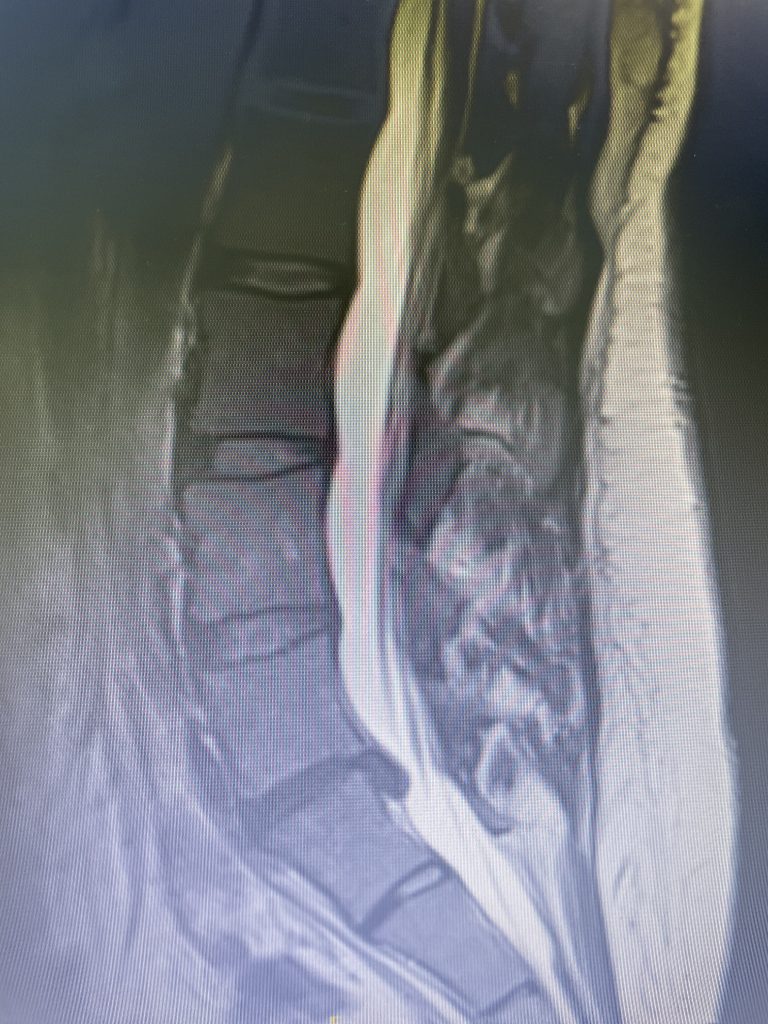

Figure 2

As a result, the patient has developed severe degenerative disc disease with collapse and a retrolisthesis above. There is also a left sided disc osteophyte complex that is causing foraminal stenosis and mild thecal sac compression. Up to this point, the patient had failed all means of conservative management including physical therapy, epidural injections, and medicine. Because of the current worsening of left leg pain another MRI was performed which demonstrated a significant increase in the disc herniation with severe thecal sac compression and nerve root compression (Fig 2). It was decided to schedule the patient for decompression, discectomy, and fusion because of the progression of disc herniation and retrolisthesis.